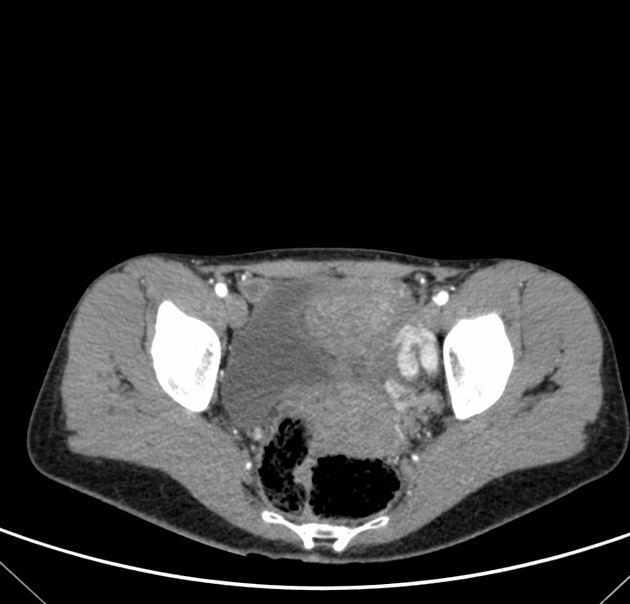

post-mictruition syncope = bladder paraganglioma

syncope when pees

MIBG-123 uptake at the bladder wall in a bladder paraganglioma

MIBG does not have renal or bladder uptake, so abnormal activity there = paraganglioma